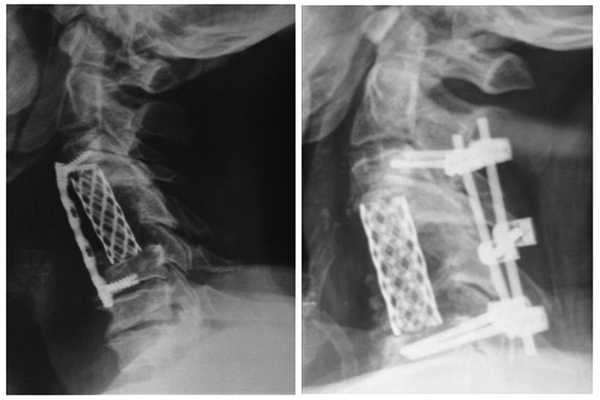

В раннем послеоперационном периоде на контрольных рентгенограммах отмечена потеря коррекции, изменение конфигурации пластины. Учитывая недостаточную плотность кости, выявленную интраоперационно, принято решение о дополнительной задней фиксации. Выполнена коррекция деформации с транспедикулярной фиксацией (рис. 5). Рис. 5. Рентген-контроль (сагиттальная проекция) до и после дополнительной коррекции и стабилизации.